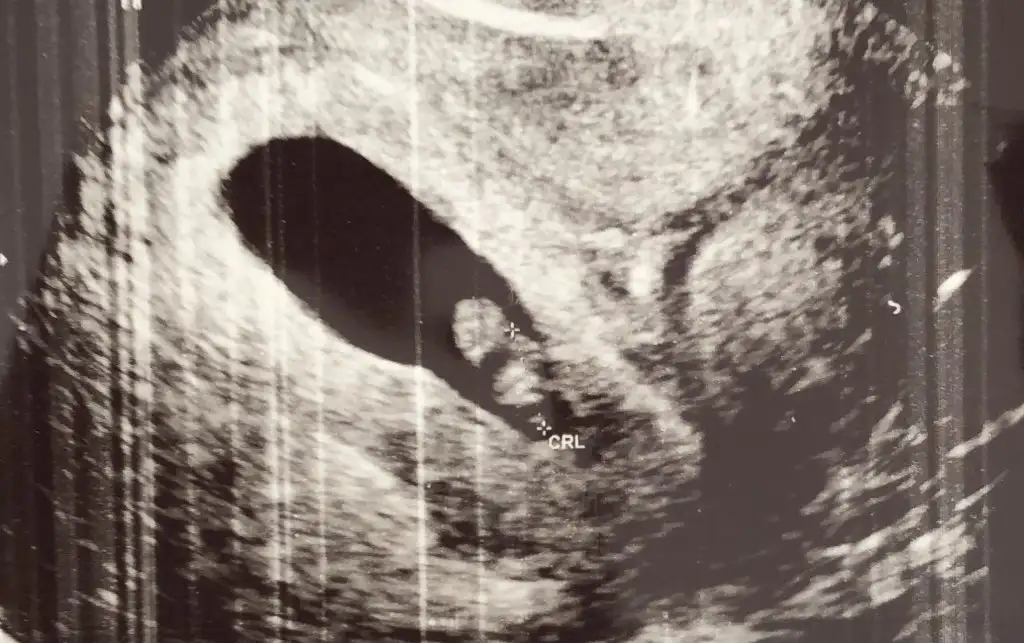

paşacık merhaba diyor sana

Hayırlısı olsun bakalımpaşacık merhaba diyor sana